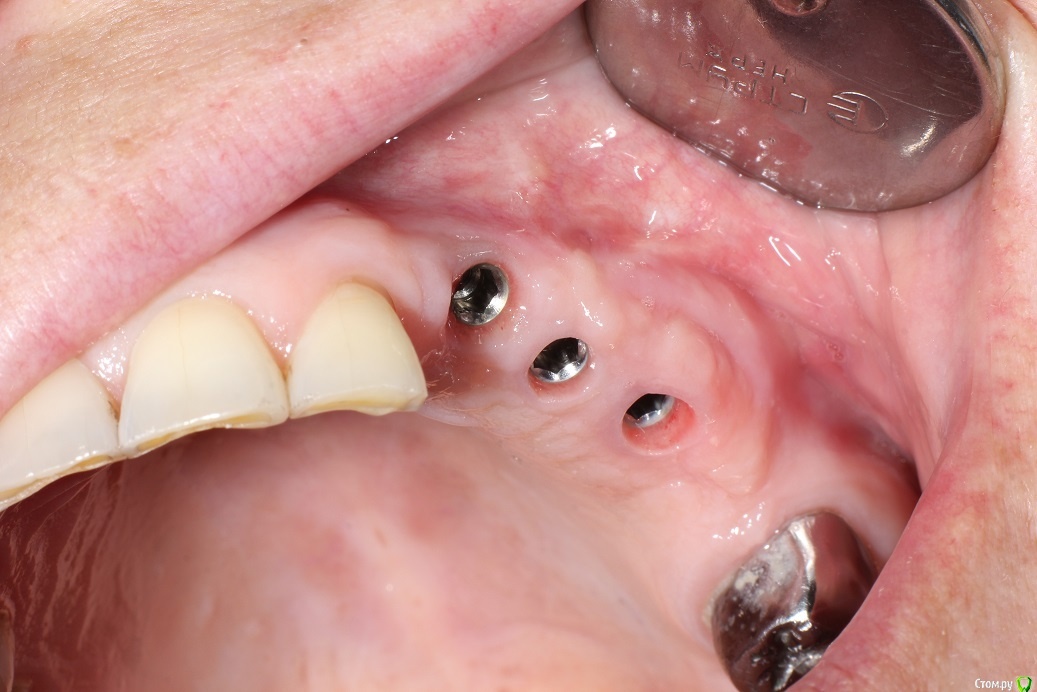

kuziy12 Опубликовано 2 ноября, 2020 Поделиться Опубликовано 2 ноября, 2020 Имплантация с синус лифтингом. Беда с позицией 2.3. Коронки на cad\cam, наносил розовую керамику и красил все сам. Сваливать не на кого) До: После имплантации: Формики: Десна: Постоянная конструкция: Улыбка: 3 Ссылка на комментарий

kuziy12 Опубликовано 3 ноября, 2020 Автор Поделиться Опубликовано 3 ноября, 2020 Шаблончики делайте)Начальству говорю - покупайте КТ. Не хотят гады. 2.6 консольный получился?да Это Вы уже импланты ставите? Умничка!А что за система, небось Ирис? MIS SEVEN Ссылка на комментарий